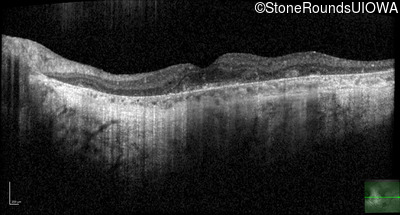

Optical Coherence Tomography - Left - 20/40 sc

Exemplar / OCT Stack